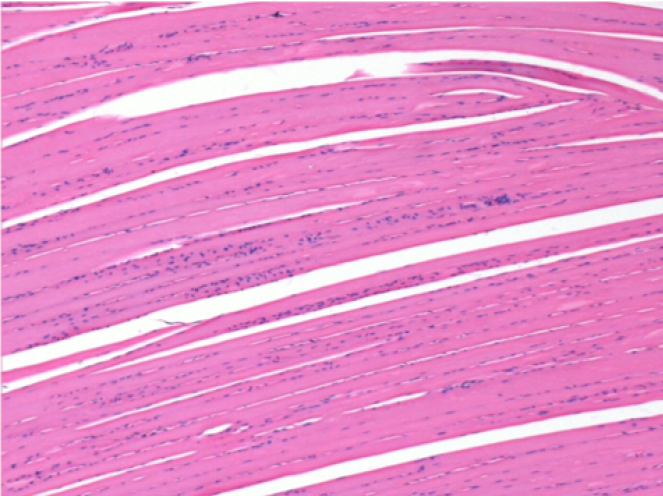

Через 10 днів після ін'єкції Ендопіл 0,1 мл в правий претибіальний м'яз.

Тут можна побачити утворення вакуолей, які оточені лімфоцитами. Вакуолі відрізняються від некрозу тканини. Присутність лімфоцитів пов'язана з проникністю клітинних мембран.